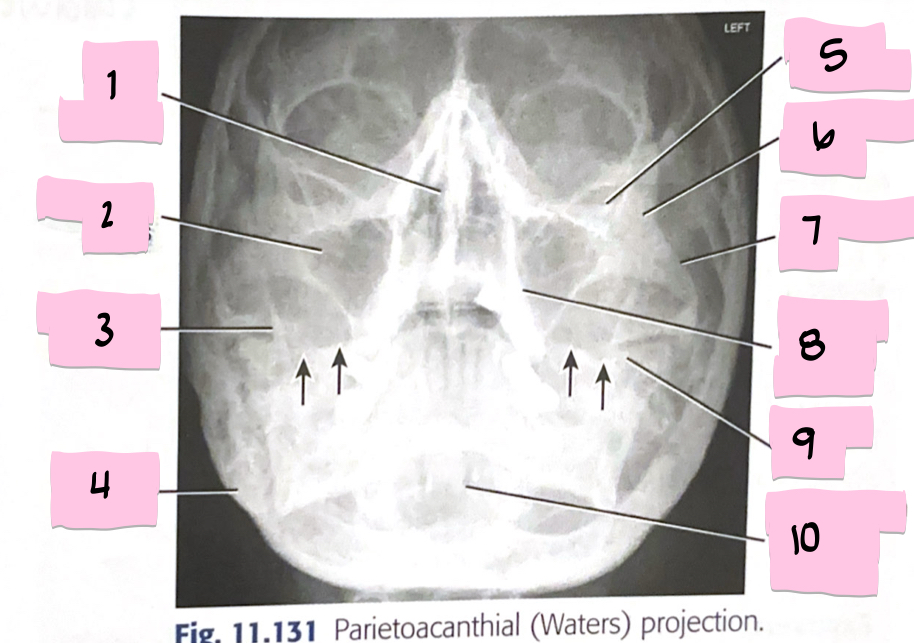

What is 1 pointing to?

Bony nasal septum

What is 2 pointing to?

Maxillary sinus

What is 3 pointing to?

Coronoid process

What is 4 pointing to?

Mastoid process

What is 5 pointing to?

Inferior orbital rim

What is 6 pointing to?

Zygomatic bone

What is 7 pointing to?

Zygomatic arch

What is 8 pointing to?

Maxillary alveolar process

What is 9 pointing to?

Petrous ridge

What is 10 pointing to?

Dens within foramen magnum